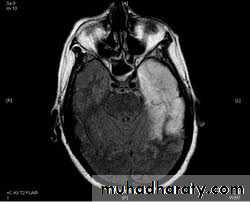

Herpes Encephalitis

Accounts for 10-20% of viral encephalitis2.3 cases per 1 million

HSV-1 >95% cases

Biphasic- 5-30, >50yrs

Primary infection or reactivation

Fever, altered mental status, bizarre behavior, seizures

Temporal lobe involved

Diagnosis: LP: Increased CSF protein, leucocytes with lymphocytic predominance and increased CSF RBCs due to hemorrhagic necrosis

CSF HSV PCR: High sensitivity and specificity

Treatment: IV Acyclovir, reduces mortality. Despite treatment mortality upto 15% with survivors with longterm cognitive impairments